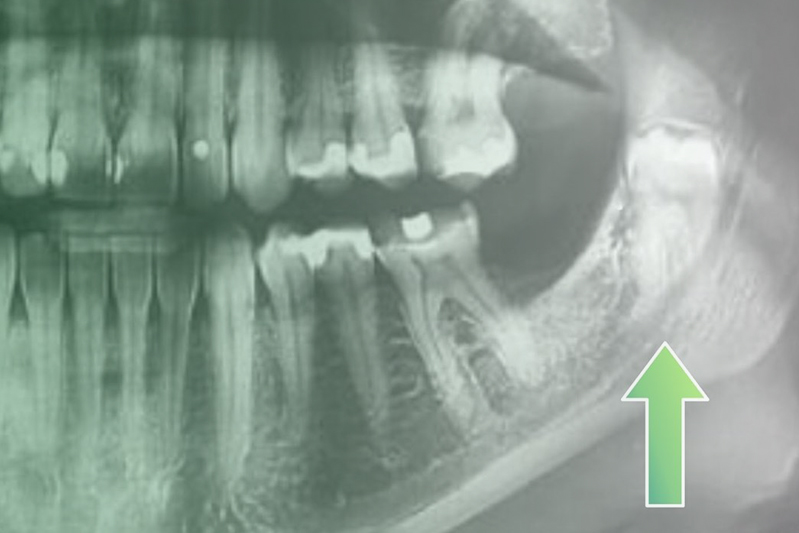

Клинический случай. Эндодонтия